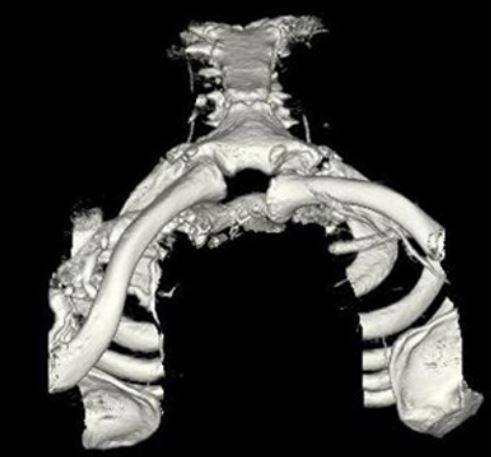

A 33-year-old secretary presents three months after a motor vehicle collision with a mild asymmetry to her sternal area and difficulty swallowing. She denies any complaints of respiratory distress or upper extremity paresthesias. Her upper extremity neurovascular exam shows no deficits. A 3-D computed tomography image is shown in Figure A. What is the most appropriate treatment for this patient?

The clinical presentation is consistent with a chronic sternoclavicular dislocation, which is defined as being greater than 3 weeks old. The 3D CT image shows posterior displacement of the medial clavicle relative to the sternum. Chronic anterior dislocations are recommended to be treated conservatively, especially if not symptomatic, but as this is a posterior dislocations, current recommendations are to treat them with reduction in order to avoid delayed issues with the medial clavicle interacting with the mediastinal structures.